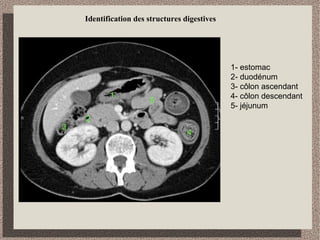

Identification des structures digestives

1- estomac

2- duodénum

3- côlon ascendant

4- côlon descendant

5- jéjunum